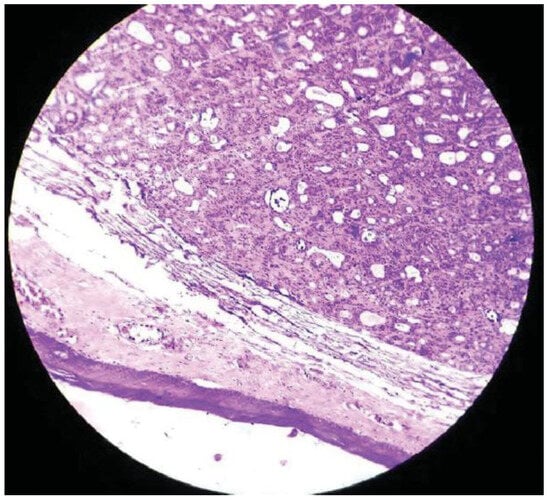

Basal Cell Adenoma of Retromolar Region from Minor Salivary Gland Origin in a 45-Year-Old Female: A Case Report

:Case Presentation